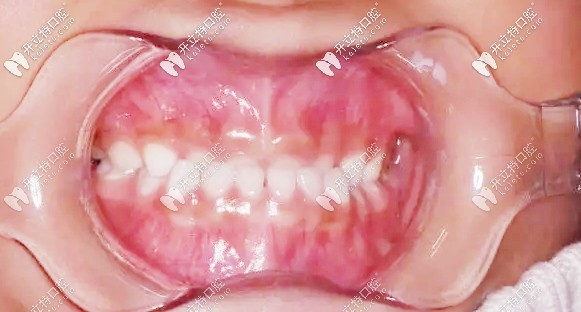

第二次復(fù)診,孩子的牙齒改善很明顯,我這顆懸著的心也算是能稍稍放下了▼

二次復(fù)診牙齒狀況

整個過程大約有10個月,孩子相對來說還算配合,矯正周期完成,結(jié)果還是很滿意的。